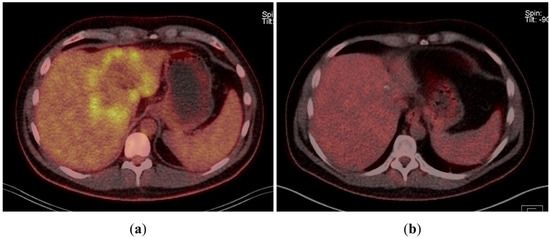

A 43-year-old man went because of persistent fatigue to the general practitioner. The diagnostic showed a large tumor within the central liver (see Figure 1a), which was biopsy-proven as a moderate-differentiated intrahepatic cholangiocarcinoma. An extrahepatic tumor spread could be ruled out (applying an FDG-PET-CT scan, see Figure 2a). Due to the invasion of the hepatic veins, which precluded a primary resection, chemotherapy with cisplatin / gemcitabine was initiated. The tumor showed a partial response (see Figure 1b). We decided to perform surgical exploration with the intent of an ex situ liver resection. Due to an invasion in liver segment VII, even an extended left trisegmentectomy was not possible. We performed an SIRT of both liver lobes resulting in a further, even metabolic (Standardized Uptake Value, SUVmean of the tumor in the initial PET scan: 7.3; SUVmean after treatment: 3.0), response of the tumor (see Figure 2a,b). The CA19-9 levels were always below the reference value. Twenty-two months after the initial diagnosis, the patient could be transplanted with a right living donor lobe from a friend. Histopathologic examination showed an intrahepatic cholangiocarcinoma with a maximum diameter of 6.3 cm. The tumor stage was ypT3, N0, L0, V0, Pn0, R0. Currently, 17 months after the LDLT, the patient is recurrence-free and in good clinical health (see Figure 3). The most recent CA19-9 level is 21.3 U/mL (reference value < 27.0 U/mL).

Figure 2. (a) Tumor in FDG-PET-CT scan at the time of initial presentation. (b) Tumor in FDG-PET-CT scan after chemotherapy and bilobar SIRT.